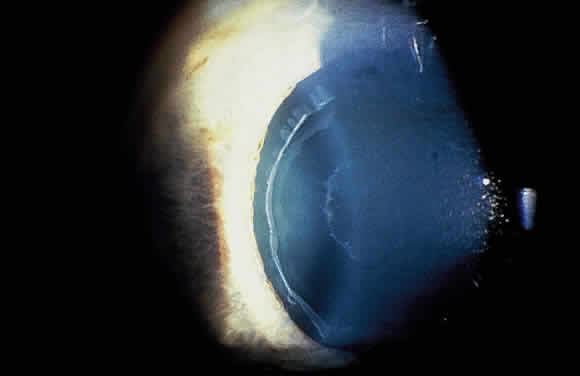

Exfoliation syndrome and pigment dispersion syndrome (PDS) are the two most common causes of increased pigmentation of the trabecular meshwork. The increased trabecular meshwork pigmentation in XFS tends to be less distinct and more patchy than the dense homogeneous deposition of trabecular pigment in PDS43 (Fig. 7). Clinically, the degree of pigmentation in XFS appears to be correlated with the severity of the glaucoma.26,69

Fig. 7. Patchy hyperpigmentation of trabecular meshwork (large arrow) in exfoliation syndrome. Faint pigment on Schwalbe's line represents a Sampaolesi's line (small arrow). Also notice exfoliative deposits in angle. (Van Baskirk EM: Clinical Atlas of Glaucoma, p 53. Philadelphia, WB Saunders, 1986)

Pigment also may be deposited on or anterior to Schwalbe's line (Sampaolesi's line). Occasionally, flakes of exfoliative material may be present in the anterior chamber angle (see Fig. 7). Although the anterior chamber angle usually is open in XFS, acute and chronic angle closure and occludable angles may be seen.9,69–71